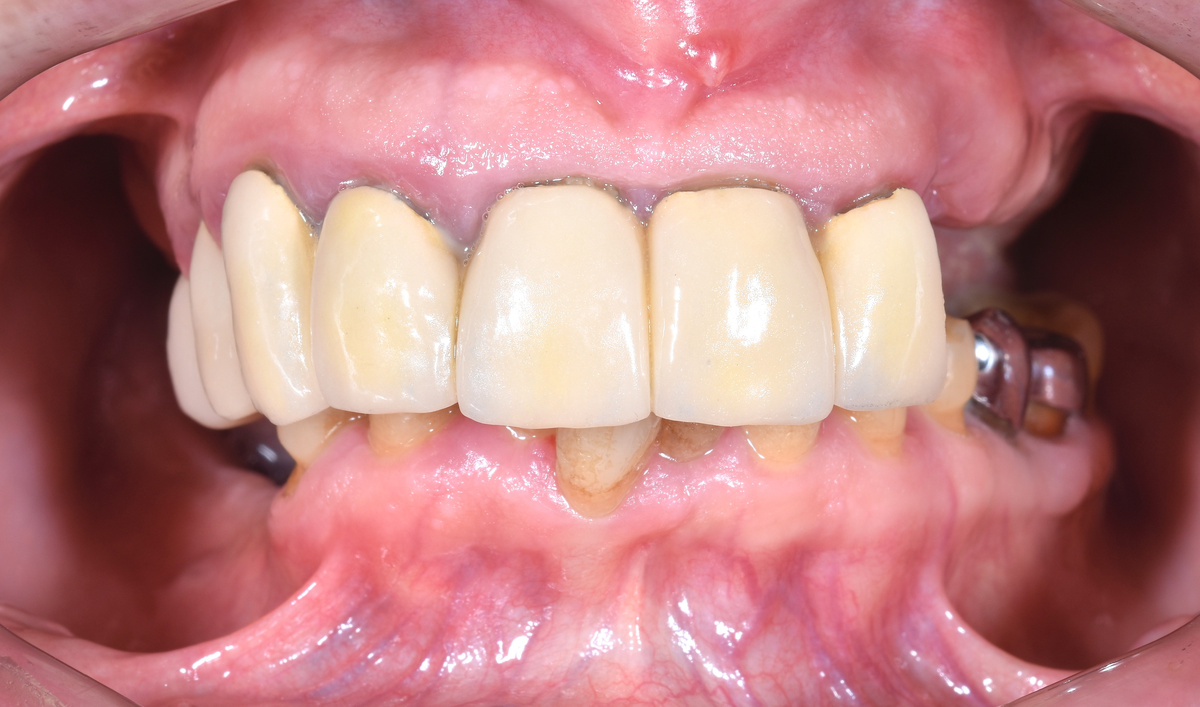

Операцию разбили на два этапа в один день. Начало в 12:00, первый этап завершён к 14:00. Сразу установили предвременный протез FP1 - без розового пластика, только для формирования контура десны.

Предвременный протез FP1 устанавливается сразу после операции. Его задача - даже не эстетика и уж точно не полноценное жевание, а формирование правильного контура десны. Ткани формируются под протезом, принимая нужную форму сразу.

Этот протез изготавливается ещё до операции. А благодаря новому интраоральному сканеру мы можем сразу же прикрутить его - быстро, потому что экономим время на этапе снятия слепков для настоящего временного протеза, который изготавливется после операции, который крепок достаточно, чтобы можно было жевать после приживления имплантатов. Таким образом, сейчас пациент не выходит из клиники без зубов - даже на один день.

Через несколько дней, когда изготовится полноценный временный протез, а десна сформируется, поменяем хлипкий на адекватный и отпустим человека домой. С нормальным постоянном пациентка будет жить несколько месяцев, пока имплантаты окончательно не интегрируются с костью.

Кровь - раны свежие:

А протез предвременный.

-8